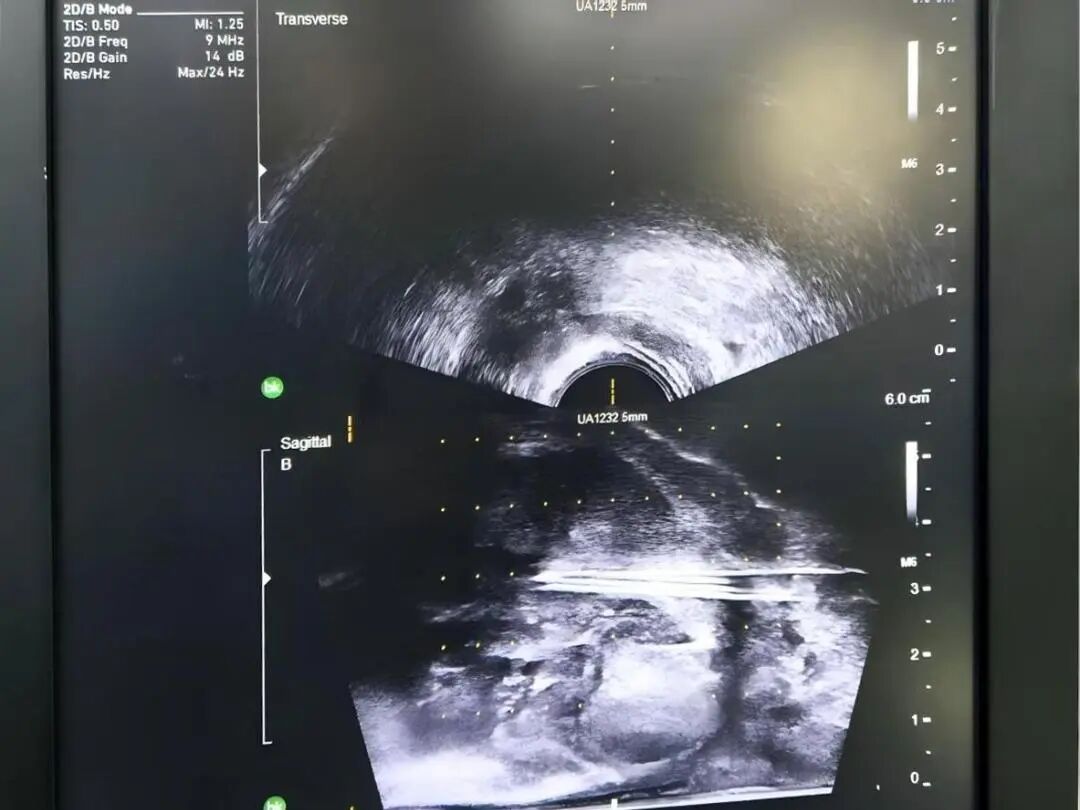

前列腺恶性肿瘤 是男性常见的泌尿系统肿瘤之一 当病情步入中晚期 治疗的关键在于结合系统治疗 一项能够直击病灶 持续作用的微创技术 为综合治疗拓展了新的可能 近日,贵州航天医院泌尿外科团队成功开展一例超声引导下经会阴前列腺碘125粒子植入术,为患者制定了个体化治疗方案。 案例分享 近期,一位年近八旬的男性患者因左侧髋部不适伴下肢放射痛前来就诊,初步检查提示可能存在前列腺肿瘤伴骨转移,为进一步明确诊断,患者随即转入泌尿外科诊治。泌尿外科为患者完善了相关检查,随后在超声引导下实施了经会阴前列腺穿刺活检,结合磁共振(MRI)影像与病理结果,最终明确诊断为前列腺腺癌(T4N0M1)。 考虑到患者年纪较大、身体状况比较弱,加上肿瘤已是晚期,已不适合创伤较大的前列腺癌根治性切除手术。为提供更佳的治疗方案,泌尿外科组织呼吸与危重症医学科肿瘤病区的专家进行了多学科讨论评估,征得家属同意后,定了一个分两步走的治疗方案:先实施前列腺肿瘤碘125粒子植入微创手术(把带辐射的小粒子放到患处杀灭肿瘤细胞),手术后,再配合药物(内分泌治疗)来控制病情。手术过程顺利,患者恢复良好,目前已出院并定期随访中。 术后植入粒子影像 我院多学科诊疗(MDT)已成为应对复杂疾病的常规模式,通过整合多学科的资源与优势,汇聚外科、内科、肿瘤、微创介入、影像、检验等多学科专家进行会诊,突出个体化治疗和综合全面治疗,提高诊疗效率和精准性,避免患者在多个科室间反复挂号奔波,缩短诊疗等待时间,让广大肿瘤、疑难重症患者享受到更加优质、专业、“一站式”的诊疗服务。 什么是放射性粒子植入技术 放射治疗是肿瘤治疗的常见手段之一,主要包括外照射与近距离放射治疗,碘125粒子植入属于持续低剂量率近距离放疗的一种,将微型放射性粒子永久植入前列腺组织内,通过持续释放射线作用于肿瘤区域,治疗前需通过影像学检查精确评估前列腺形态、体积,并制定个体化的剂量分布计划,术中在超声实时引导下植入粒子,以便根据实际情况调整进针路径与剂量分布,尽量使射线覆盖前列腺及其周边一定范围。该技术通常适用于部分局部进展性或转移性前列腺肿瘤患者,可作为综合治疗策略中的一环。 放射性粒子植入技术优势 1.能够把粒子准确植入肿瘤中,定位精准,靶向性强,高度适形。 2.肿瘤接受的放射剂量明显增加,而不增加正常组织的剂量。 3.持续低剂量率放射,能对不同分裂周期的肿瘤细胞进行不间断照射,提高了放射敏感性,累计射线剂量可达外放疗的2~3倍,有较高的放射生物效应。 4.粒子植入的部位肿瘤组织可被杀灭,距粒子1cm以外的正常组织几乎不受损伤,能有效降低正常组织受照剂量,正常组织损伤小,几乎不造成白细胞下降、骨髓抑制、胃肠道反应、脱发等副作用,病人无痛苦。 5.粒子外壳为钛合金,与人体有很好的组织相容性,不会产生排异及放射泄漏。 6.与其他的肿瘤治疗方法相比,创伤小、生活质量高、住院时间短。 7.能与手术、化疗及外放疗配合互补提高疗效。 注:本文仅为医疗技术介绍,具体治疗方案请务必咨询临床医生,并结合患者个体情况制定。部分图片来源于网络,如有侵权,请联系删除。 贵州航天医院 泌尿外科专家简介 石 英 泌尿外科党支部书记、主任,主任医师 中国医师协会泌尿外科分会感染协作组委员,奥林巴斯泌尿系软镜西南区专家组成员,西南地区第一批输尿管软镜专家组成员,贵州省医学会泌尿外科分会委员,贵州省性学会理事,贵州省性学会常务委员,贵州省泌尿外科专业医疗质量控制中心专家委员会委员。 从事泌尿外科专业近30年,熟练掌握泌尿系各类疾病的诊治,具有丰富的临床经验,擅长泌尿系结石、腹膜后肿瘤及泌尿系肿瘤的手术治疗,对泌尿系感染、泌尿系结核、尿源性脓毒血症的救治有独到的见解及抢救经验,在贵州省率先引入输尿管软镜技术,同时在男科领域,对男性阳痿、早泄及前列腺疾病有很深的研究。 李国成 泌尿外科副主任,副主任医师 中国人体健康科技促进会男科学专业委员会委员,贵州省性学会泌尿外科分会委员,贵州省医学会男科学分会委员,遵义市医学会男科学分会副主任委员兼秘书长,遵义市医学会泌尿外科分会常务委员,贵州航天医院男科带头人。 从事泌尿外科及男科工作10余年,曾多次前往上海交通大学附属第一人民医院、中国中医科学院西苑医院进修学习男科;擅长性功能障碍的诊治、男性整形手术、前列腺增生激光手术、显微手术等。 李 凯 中共党员,泌尿外科副主任医师 贵州航天医院肿瘤腔镜组带头人,擅长肾癌根治术、输尿管癌根治术、膀胱及前列腺癌根治术、腹腔镜输尿管狭窄切除吻合术、输尿管切开取石术等手术,在遵义市率先开展泌尿系结核后膀胱挛缩全腹腔镜下膀胱扩大术。 贵州省医学会泌尿外科分会青年委员,遵义市医学会男科分会常务委员,遵义市医学会泌尿外科分会常务委员。 贵州航天医院泌尿外科简介 • ✦ 基本情况 ✦ • 贵州航天医院泌尿外科创建于20世纪60年代,经过几代人的努力,微创与内镜手术占比达90%以上,科室亚专业框架完善。是贵州省临床重点专科建设单位、北京清华长庚医院李建新教授团队诊疗及会诊中心、北京医学会尿路修复与重建诊疗及会诊中心、上海公济泌尿外科集团遵义中心、上海援黔专家李铮教授男科工作室、贵州省泌尿外科质量控制专家委员单位。 • ✦ 专科特色技术 ✦ • (一)泌尿系结石内镜碎石技术 泌尿系结石微创治疗领域方面是贵州省首家引进科医人钬激光碎石技术科室,在遵义地区率先掌握输尿管硬镜、软性镜,经皮肾镜钬激光碎石技术。目前是北京清华长庚医院泌尿外科“手把手”经皮肾镜碎石技术培训基地、贵州省输尿管软镜培训基地。 1.负压吸引可弯曲软镜鞘电子软镜碎石术 2.标准与超微通道相结合的经皮肾镜碎石取石术 (二)微创腹腔镜技术 泌尿外科腹腔镜技术师承于浙江省人民医院、北大、北京解放军总医院。目前采用经腹、经后腹双入路法的腹腔镜技术完成肾部分切除、肾切除、肾输尿管全长切除、肾盂输尿管成形、输尿管狭窄吻合、膀胱翻瓣等手术。在遵义地区率先掌握腹腔镜下膀胱癌根治术、腹腔镜下前列腺癌根治术。 (三)男科、盆底技术临床应用 遵义地区男科分会主委单位,是贵州省首家引进尿动力学检查并取得了全国资质认证科室,也是贵州省首家进行RigiScan检查的单位。在遵义地区率先掌握显微取精子技术以及显微镜下治疗精索静脉曲张、显微镜下输精管吻合、输精管附睾吻合技术。率先采用前列腺激光剜除术治疗前列腺增生症。在陆军军医大学西南医院泌尿外科主任沈文浩教授指导下,完成遵义市首例神经源性膀胱骶神经调节刺激器置入术。 • ✦ 诊疗范围 ✦ • 诊疗范围(除外肾移植、癌栓):泌尿系结石、泌尿系肿瘤、肾上腺疾病、肾积水、前列腺增生、男性生殖器功能障碍(精索静脉曲张、生殖道感染、输精管梗阻等)、盆底功能障碍性疾病(膀胱脱垂、排尿功能异常、尿失禁)、泌尿生殖系畸形。 泌尿外科拥有独立门诊治疗室、日间手术室、尿动力学检查室、精液分析检查室、男性勃起功能检查及治疗室、ESWL治疗室、结石分析检查室。